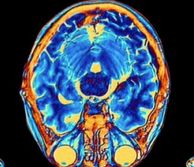

Coloured MRI scan of human brain

New research counters dominant view in neuroscience

Study published in Nature Neuroscience, co-led by Prof Bill Wisden, suggests toxin clearance is reduced during sleep, rather than increased

Scan of brain

New Research on Type 2 Diabetes and Dementia

New research may help explain why people with type 2 diabetes are more likely to develop dementia.